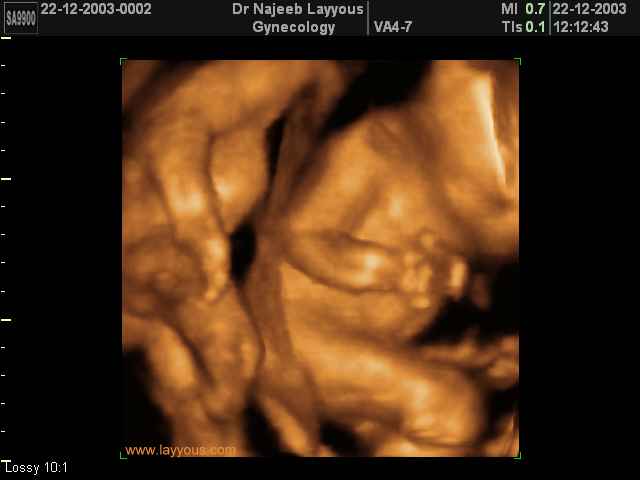

شوفوا صور التراساوند حقت التوينز

هنا حمل توينز عمره 5اسابيع

اجنة توام عمرهم سبع اسابيع

اجنة توام عمرهم 11 اسبوع

شوفوا هذول واحد يدف اخوه يا حلوهم